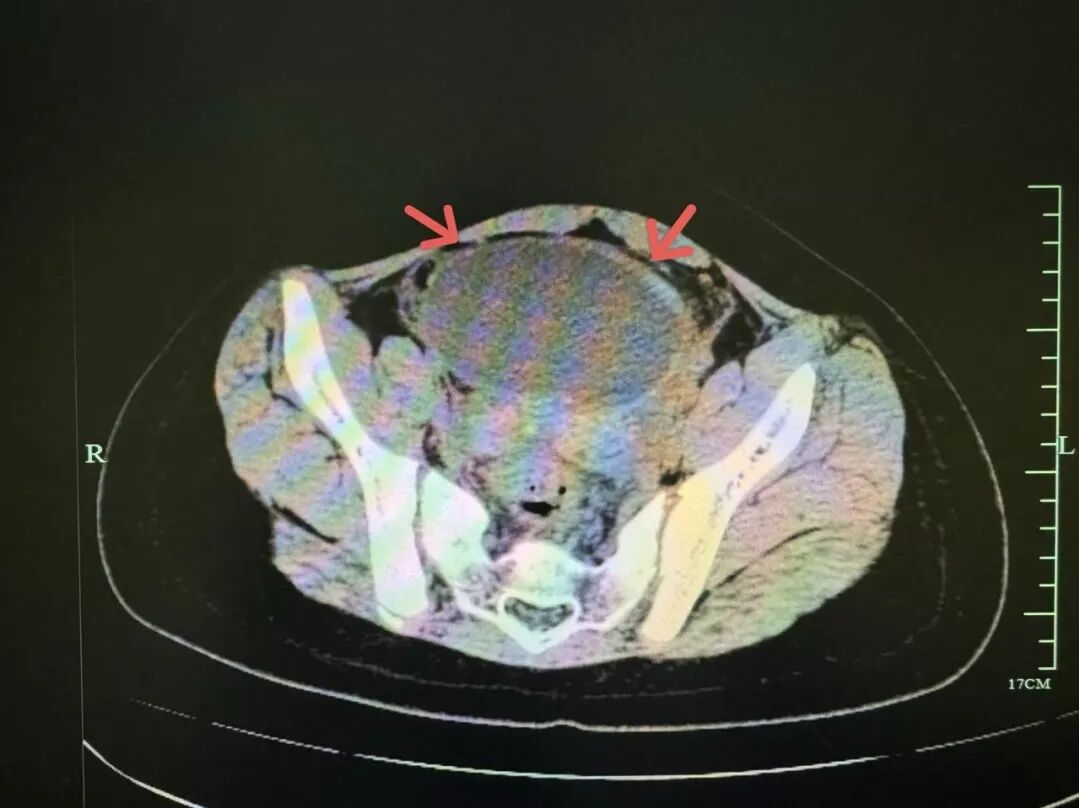

然而,小吉的病情出现了「可疑」的变化:呕吐好了,但肚子还疼,复查感染指标反而更高了!这个现象拉响了儿科医生心中的「警报」,立即启动更深入的排查,最终将目标锁定盆腔时,真相浮出水面:B 超和 CT 显示,小吉的盆腔内藏着一个约 9.5 cm 的巨大卵巢囊肿,并且已发生了 「蒂扭转」!这是一种需要紧急手术的妇科急腹症!

万幸儿科团队及时诊断,妇产科团队紧急手术,手术十分顺利,保住了小吉的卵巢,避免了不可逆的伤害。